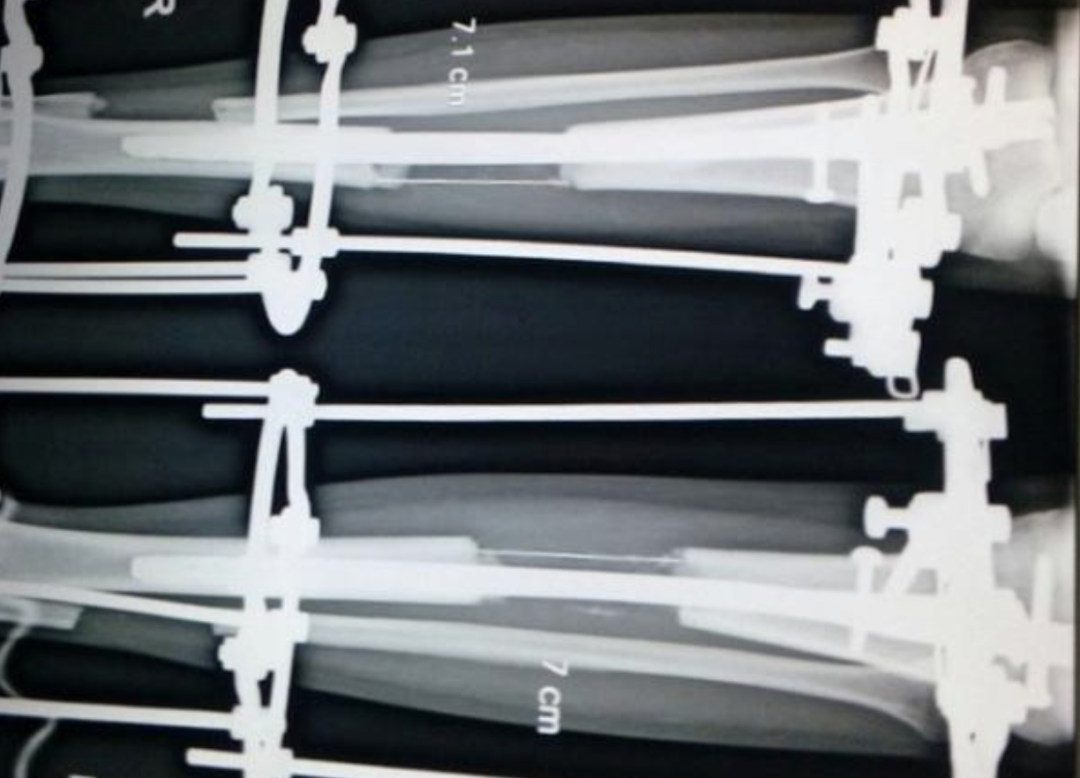

曾有医生做绝育手术导致15人死亡,“增高手术”的乱象也让人震惊。据《BBC》报道,在印度恰蒂斯加尔邦,一名医生由于涉嫌在两个国立绝育手术中心中做手术时,出现严重手术失误,导致15名妇女死亡,随后遭到逮捕。据悉,古普塔医生(Dr RK Gupta)和他的助手分别在两个绝育中心为130名妇女实施输卵管切除手术。在比拉斯布尔的绝育中心,有14位妇女在手术中死亡。而在第二个绝育中心,则有一名患者死亡。同时,还有超过90名妇女依然留院观察,其中有一部分人还没脱离危险状态。此次医疗事故已经引起了民众的游行抗议。印度政府已经下令为此事展开调查。事故原因至今尚不清晰。古普塔随后被警方逮捕,而他法庭上表示,“这不是我的错,有关部门对我施压,要求我必须完成目标计划。手术其实完成得很好,问题是出在给这些患者的用药上面。”据悉,在绝育中心,古普塔于5个小时内为83位妇女完成了绝育手术。而政府规定手术医生一天最多只能进行35个手术。法庭信息显示,当这些妇女在手术后被送达医院急救时,她们不仅持续地呕吐,而且血压还下降得非常严重。绝育手术是在一个白色的建筑物中完成的。建筑周边十分荒凉,野草丛生。这是一个由慈善组织建造的医院。但当地人说,它早已对外关闭,如今仅作为政府卫生营使用。走进中心,天花板和墙上的蜘蛛网随处可见,地上铺满灰尘。而这就是83位妇女被实施绝育手术的地方。据《The Guardian》报道,价格相对低廉的印度增高手术吸引了印度本土以及来自欧美的大量人群。然而,印度的增高手术市场却缺乏有效的监管并且许多医师都缺乏手术经验。而这一“增高手术”,其实质是将患者的腿骨“打断”,并在腿部外面架上支架,直到患者能再次行走。科玛尔(Komal)今年24岁,来自印度西部一个名叫Kota的城镇,在去年进行了增高手术后,她“长高”了8厘米。为科玛尔做手术的医生是沙林(Amar Sarin),他在德里长期从事着增高手术行业。科玛尔不会告诉她的朋友,去年她“消失”的那6个月里她去了哪里。为了支付她增高手术的费用,科玛尔的父母不得不卖掉家里的土地,但对科玛尔来说,这一切都很值得。“我现在有了信心。我以前只有1.37米高。人们一直取笑我,我也找不到工作。现在我的妹妹也在做增高手术。”接受了增高手术的患者们。图源:The Guardian《The Guardian》称,印度增高手术高需求的背后是长期以来形成的“高个子比较有吸引力”的观念。许多印度青年正选择通过增高手术来获取理想的工作与婚姻。而在印度进行一项美容手术的花费只需欧美国家同类手术的五分之一,这大大吸引了欧美国家有需求的人群前来印度手术。然而,沙林医生表示,“增高手术是美容手术中最难的几种之一。但许多医生只经过了1到2个月的实习就草草上岗。很多时候,指导他们的老师也缺乏手术经验。目前还没有针对增高手术的专门培训机构或是学校,也没有正式的培训项目。”沙林还称,一位于2015年接受增高手术的男性在手术前接触了大约20位医生才决定了合适的手术执刀医生。这名接受过手术的男性表示,“许多医生都只进行过一两次增高手术,有些甚至从未亲自完成过手术。所以,我花费了一年的时间才找到合适的医生来实施手术。”印度整形外科主席医生卡普尔表示,“除非在极特殊的情况下,我们不推荐人们进行增高手术。增高手术还没有进入惯常手术的行列并且手术极有可能会引发并发症。”即便如此,印度的增高手术还是客源不断。据估算,医疗旅游项目每年能为印度带来约30亿美元的收入。而这其中很大一部分就来自美容手术。沙林表示,自5年前自己开始实施增高手术,他已经接待了超过300名增高手术客人。而这其中,只有三分之一是印度本土居民。他在朋友小奥的蛊惑下来到当地医院“体检”,没想到直接被麻醉并抬上了手术台。醒来后他才得知,自己被进行了变性手术,现在自己已经是“女儿身”了。而小奥表示,穆贾希德现在只能和自己结婚,自己将抢夺他父亲的土地,并和他远走高飞。随后,得知事情的穆贾希德父亲将小奥告上了法庭,印度医院的手术乱象就就此浮出水面。